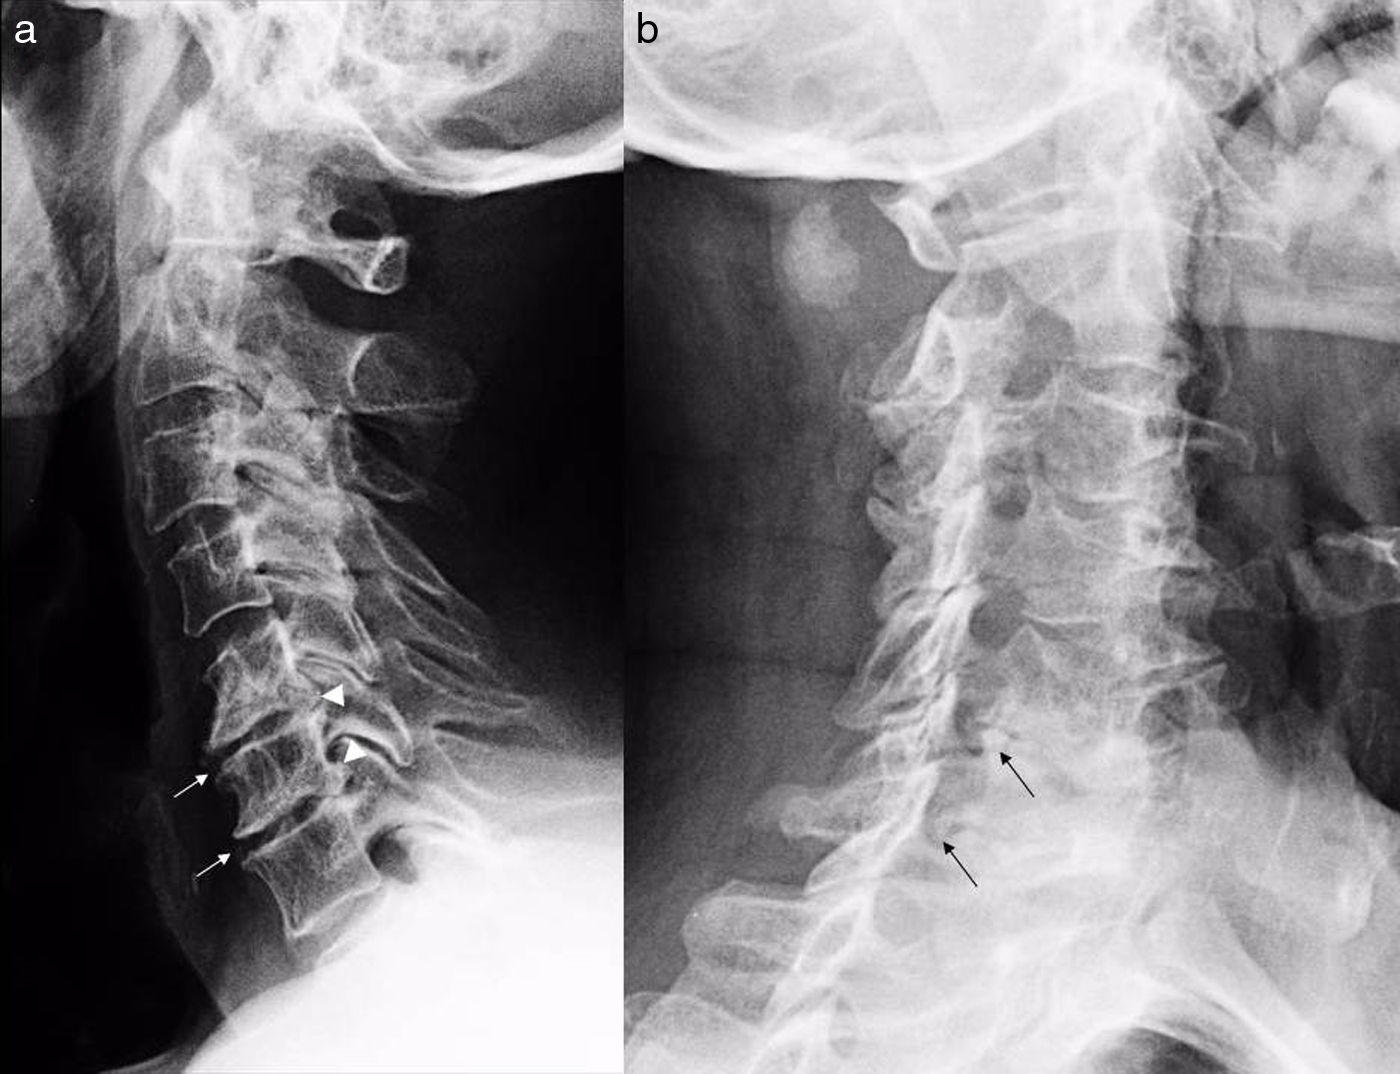

La columna vertebral es una estructura ósea que se compone de 33 vértebras superpuestas las unas sobre las otras.

Ésta protege a la médula espinal y soporta la cabeza y el tronco.

Por lo que no hay ningún tipo de vida posible sin este órgano vital del cuerpo humano, ya que es el que alberga la mayor parte del sistema nervioso central que desciende a lo largo del canal vertebral.

La columna vertebral se compone de 33 huesos apilados los unos sobre los otros.

La columna vertebral da el apoyo principal a tu cuerpo, te permite estar de pie, doblarte, girarte y protege a la espina dorsal de las lesiones.

Los músculos, los huesos sólidos, tendones, ligamentos flexibles y los nervios hacen que la columna vertebral se mantenga sana.

Sin embargo es una de las estructuras que se ve más afectada en un accidente, una lesión o una enfermedad que puede causar fuertes dolores.